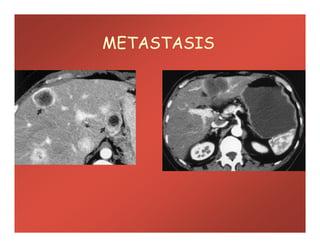

METASTASIS